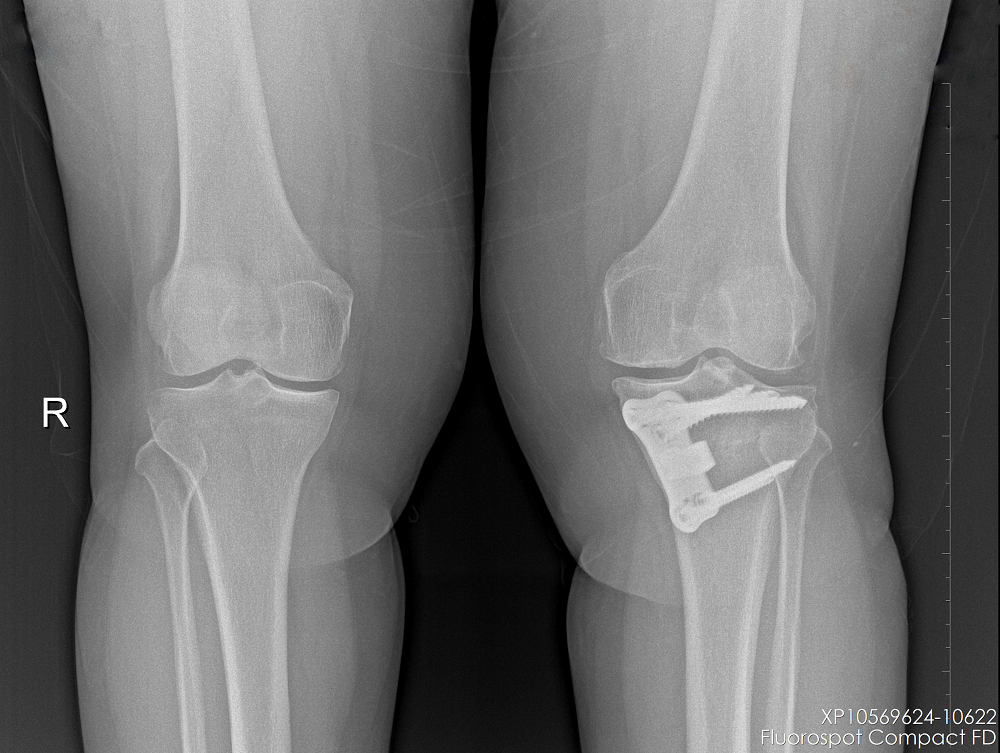

Gonartrozu olan hastanın ameliyat öncesi ve YTO yapıldıktan sonraki grafileri

Bu ameliyat sırasında tibianın ya iç ya da dış tarafında kemik kesilir. İç taraftaki kesi arasına üçgen şeklinde kemik kama yerleştirilir ve plak ve vidalarla tespit edilir. Tibianın dış tarafındaki kesiden ise uygun ebatta bir kemik kama çıkarılır.

Böylece iç taraftaki kemik kesisi konulan kama ile açıldığında veya dış taraftaki kemik kesisi çıkarılan kama ile kapatıldığında bacak düzelir. Bu, dizin sağlıklı tarafındaki eklem aralığını daraltır ve hasarlı, artritli taraftaki eklem aralığını açar. Sonuç olarak diz ağırlığı daha eşit bir şekilde taşıyabilir ve ağrılı taraftaki baskıyı hafifletebilir.